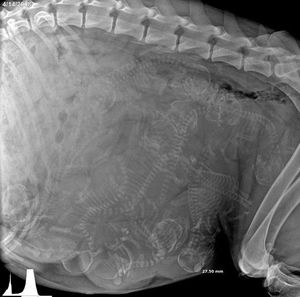

baby boom 😅

Xray of a pregnant dog